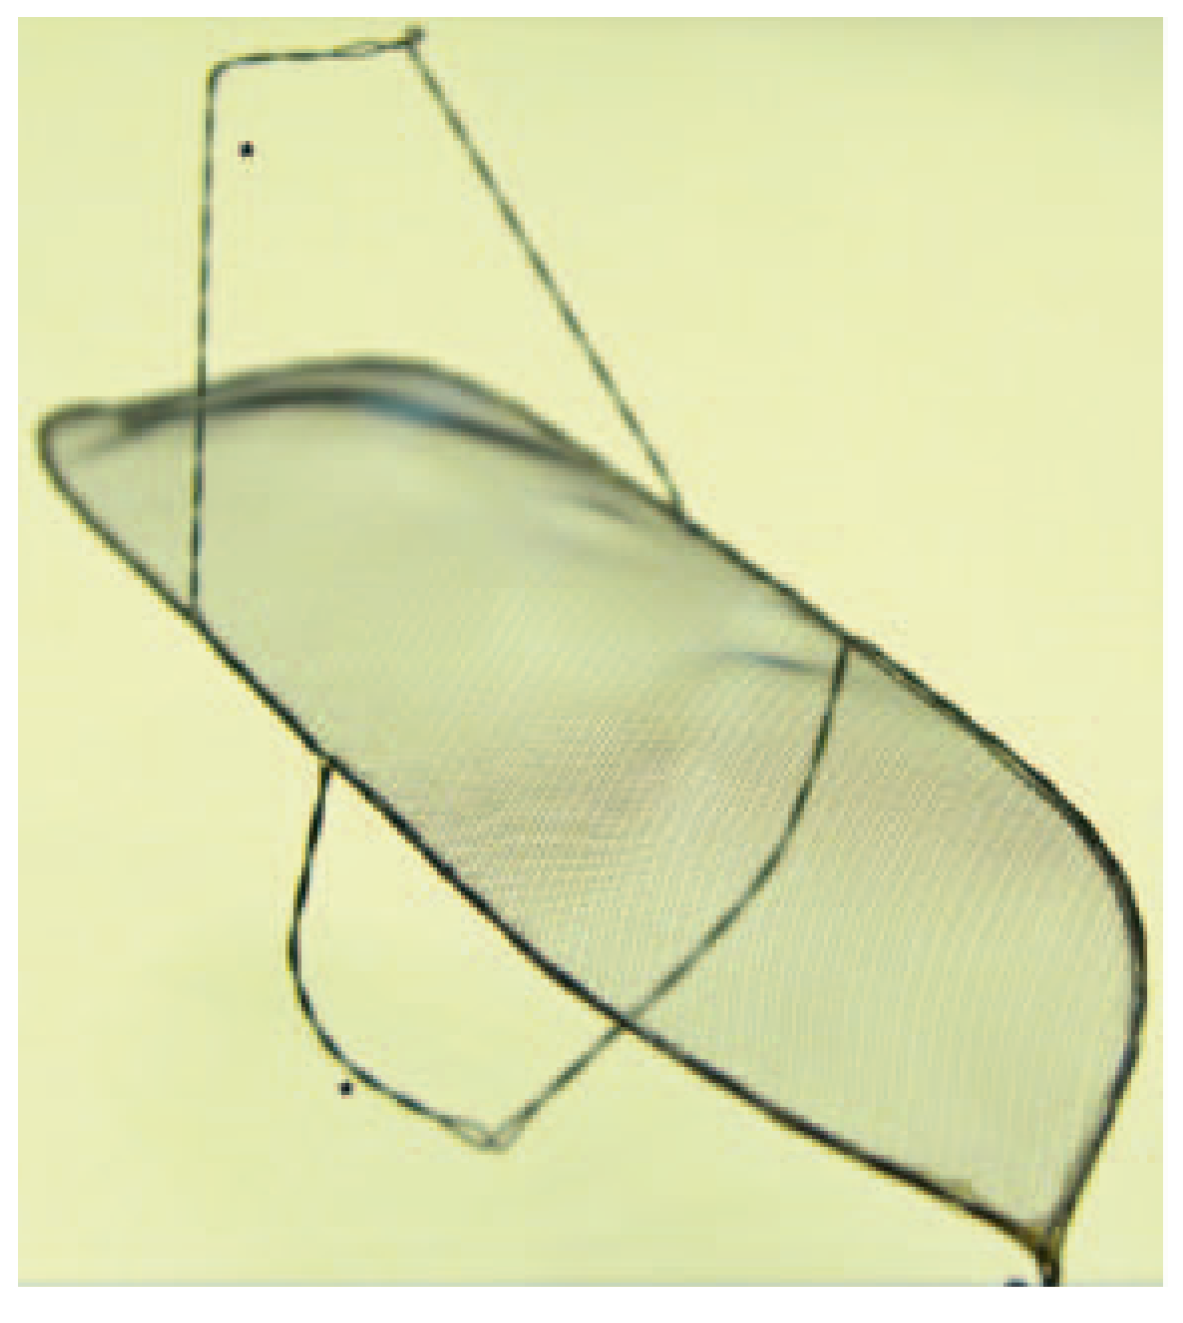

Keystone Heart Embolic Deflection Device (EDD)

The EDD (Keystone Heart Ltd, formerly SMT Research & Development Ltd, Herzliya, Israel) is introduced via femoral access (Figure 3). It is a very similar device as the Embrella, also deflecting rather than capturing emboli (Figure 2). However there are some important differences: The device fits through a 7 French sheath, however, a 9 French sheath is often used, to facilitate recapturing of the device and allowing simultaneous placement of a pigtail through the same sheath. The device is self-positioning at the outer curvature of the aortic arch covering all three neck vessels. It is anchored in the brachiocephalic trunk and the inner curvature of the aorta by stabilizing nitinol arms. Femoral access and minimal interference with the brachiocephalic trunk are potentially less traumatic than advancing a device through the brachiocephalic trunk.

Figure 2. Keystone Heart Embolic Deflection Device. The device consists of the deflection shield and two nitinol hoops (*). (Courtesy of Keystone Heart Ltd, Herzliya, Israel.